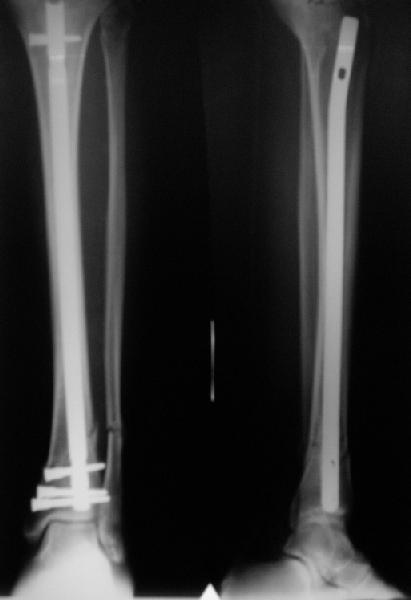

Сделали все-таки стержнем. На всякий случай просверлил дополнительное проксимальное отверстие, так что получилось три 45-градусных винта.

В дистракторе провеи спиц поболше в прокисмальном отделе, чтобы не разобщить фрагменты при сгибании колена. Комментарии и критика приветствуются.

We proceeded with nailing using a small wire distractor, with few wires at the proximal end to prevent displacement with forced knee flexion. Images attached. Comments and critics are welcome.

It is often a problem nailing upper tibial fractures. There is a tendency to apex anterior angulation as well as valgus alignment. Your entry point on the AP view seems to have been kept the same. How did you manage to maintain alignment? Any intra-operative pictures of your technique?

The lateral view shows your entry point to be quite posterior and I think this is recommended to avoid anterior angulation. Were you concerned about intra-articular penetration?

Overall an excellent post-op x-ray. Well done.